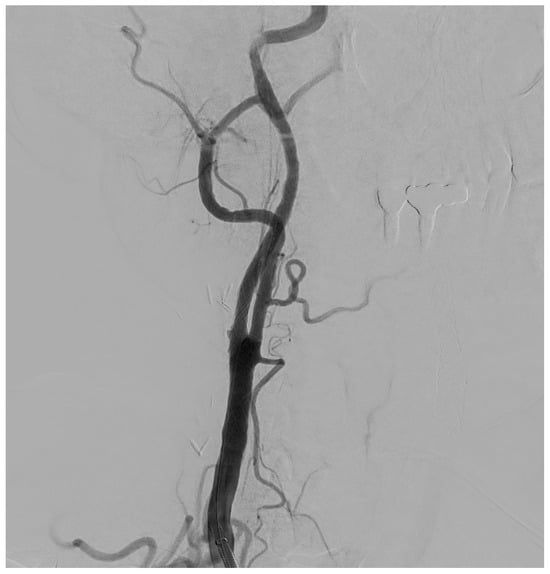

Among other diagnostic tests available for the evaluation of carotid stenosis, CT is often a second-choice test, performed as an adjunct to US. CT allows a more accurate and precise assessment of both plaque morphology and the degree of stenosis and, being relatively standardized across institutions and platforms, is not affected by operator influence. In addition, by providing a panoramic view of the entire vascular circle of the head and neck district, it allows us to analyze, in a single acquisition, both carotid arteries and the intracranial arterial circle, not accessible by ultrasound; moreover, it could be used for planning revascularization therapies thanks to reformatting software like MPR (Figure 2) and Volume Rendering (VR) (Carestream, ImageView Software, version 2.1, 150 Verona Street, Rochester, NY, USA).

Figure 2. Oblique Coronal (A) and Sagittal (B) reformation performed for preoperative planning, which shows a mixed component plaque, determining stenosis of at least 50% in the right ICA in the post-ostial tract.